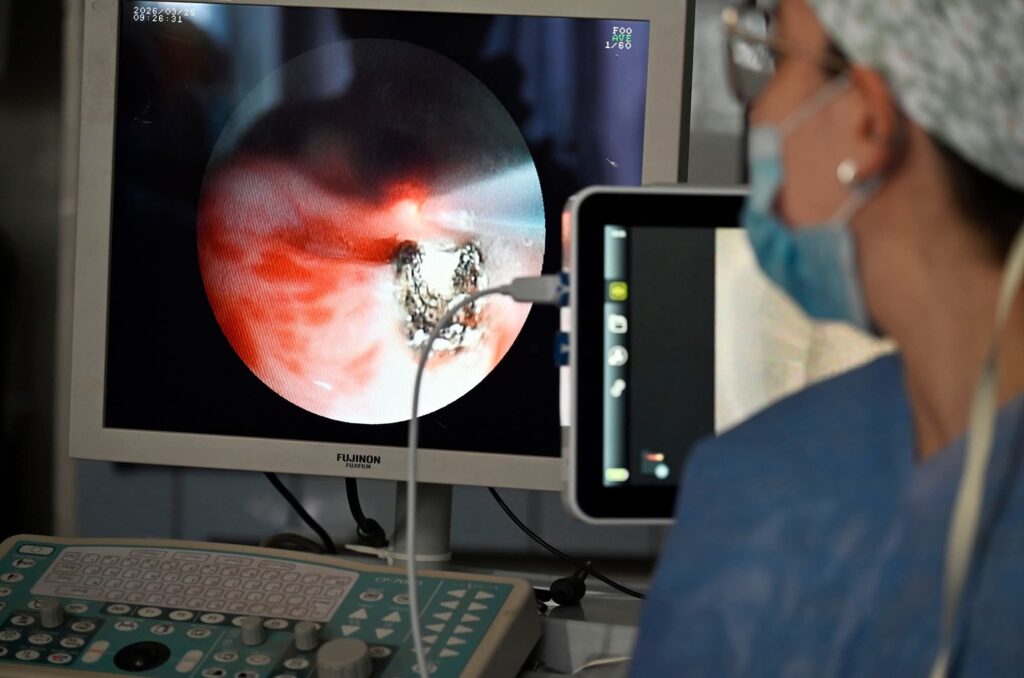

El Hospital Posadas incorporó un láser de diodo para videobroncoscopia, una tecnología que permite realizar microcirugías de alta precisión por vía endoscópica, evitando en muchos casos intervenciones tradicionales más complejas.

Este equipamiento resulta clave para el tratamiento de patologías frecuentes como la estenosis de la vía aérea —por ejemplo, posterior a una traqueostomía— y tumores de la vía aérea, que pueden ser abordados o extirpados mediante esta técnica mínimamente invasiva.